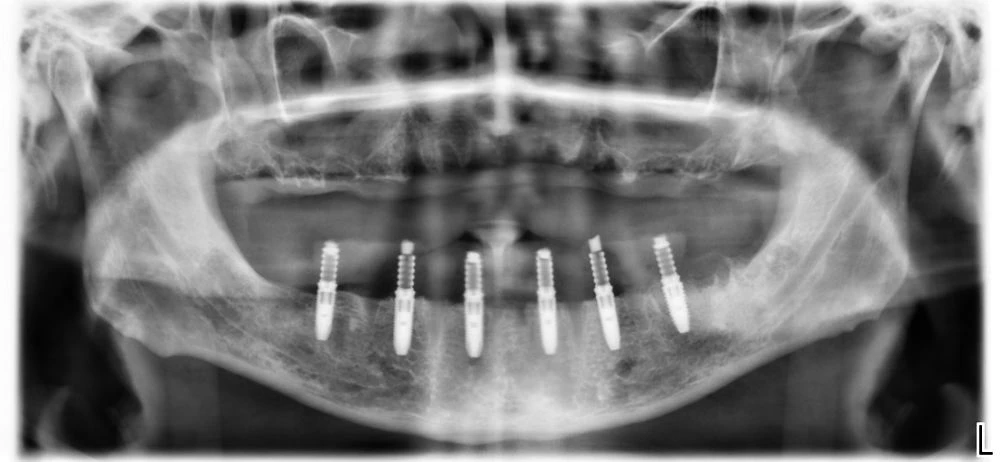

Ето как изглеждат на RO графия зъбните мостове, завършени от пластмаса, металокерамика и цирконий.

RO пластмаса – Временната пластмасова конструкция не се вижда.

/зъбните импланти са поставени с хирургичен водач/